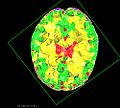

Most registration methods treat tissue parameters as uniform over the image domain. For instance, when brain tissue is modeled as an elastic material, identical stiffness parameters are used for all tissue types (CSF, GM, WM). We let different tissue types take on varying stiffness parameters, so we can thereby optimize the deformation as well as the stiffness parameters at the same time. Our approach models the tissue with a linear elastic Finite Element (FE) model and solve for the linear elastic tissue parameters as well as the deformation through a Markov Chain Monte Carlo process.

However, to accurately model the tissue, we require a tissue dependent tetrahedral mesh. Assuming we have a segmentation of the brain tissue into CSF, GM and WM, we need a mesh where the tetrahedra conform to the different tissue types (the edges of a tetrahedra do not cross from one tissue type to the other but are either fully within a tissue type or on the boundary between two tissue types).